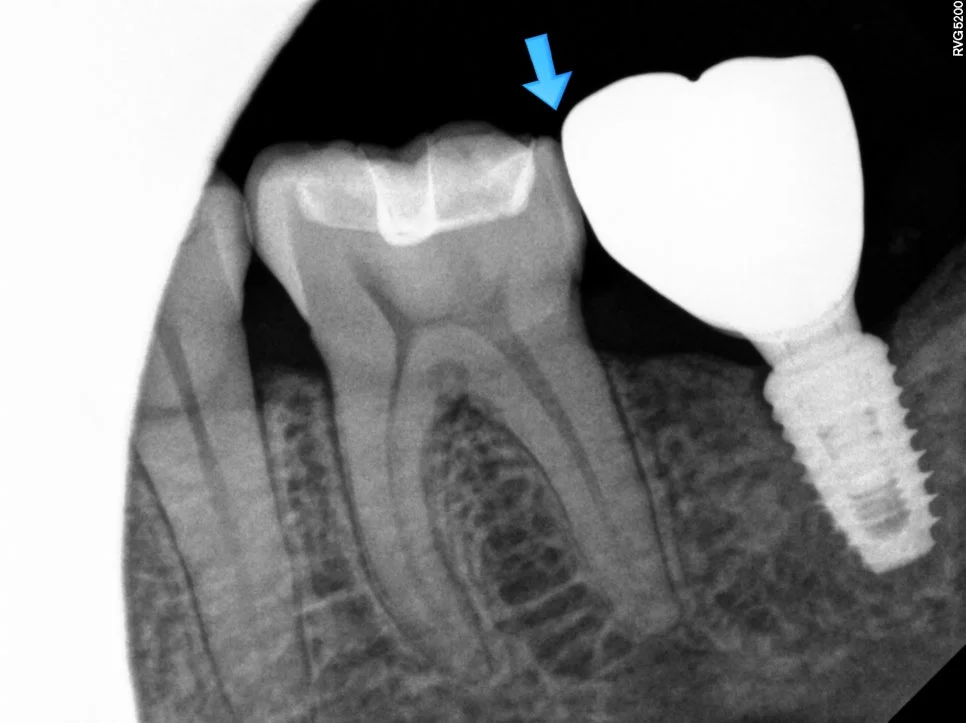

임플란트 틈새 진단 방사선 사진

X-ray에서 임플란트와 치아 사이 틈 확인

임플란트 기둥 크라운 재제작 과정

임플란트 뿌리는 그대로, 기둥과 크라운만 재제작

사진을 찍어보면 명확하게 임플란트와 치아 사이에 틈이 보이는데요. 이 정도 공간이면 음식물이 정말 엄청나게 끼게 됩니다ㅜ

앞 자연치가 충치 없이 깨끗하기에 → 임플란트 보철물을 재제작하기로 합니다.

임플란트 뿌리는 그대로 둔 채 기둥과 머리만 새로 제작합니다^^

긴밀해진 사이 틈 — X-ray로 확인

긴밀해진 사이 틈을 육안으로도 X-ray로도 확인할 수 있고, 주변 잇몸도 예쁘게 아문 것을 확인할 수 있습니다^^